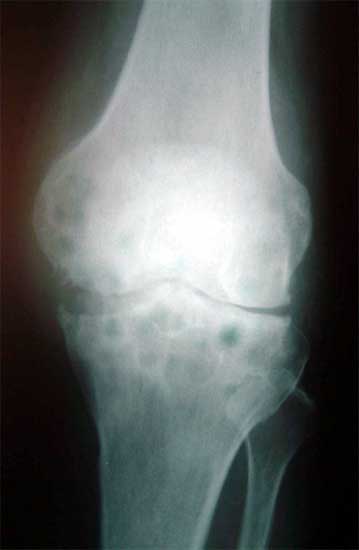

复合BMP的脱钙异体骨基质填充骨缺损      复合BMP的脱钙异体骨基质修复骨缺损,膝关节置换术后